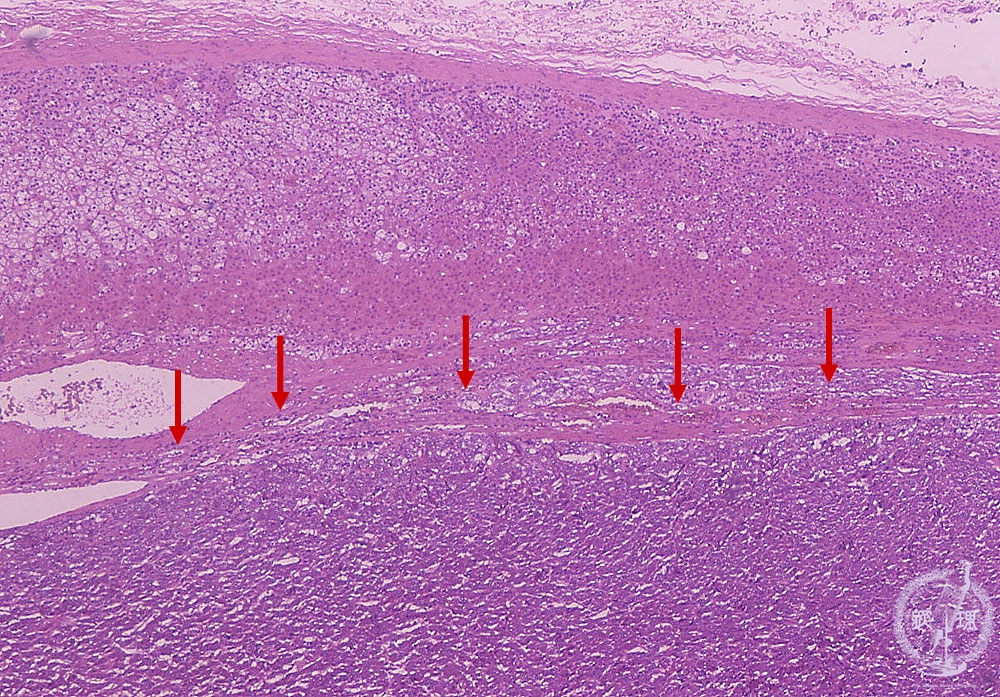

- ★(14)Pheochromocytoma

Microscopic findings (HE stain, low power view). Proliferation of the tumor cells (arrows) in the medulla of the adrenal gland.